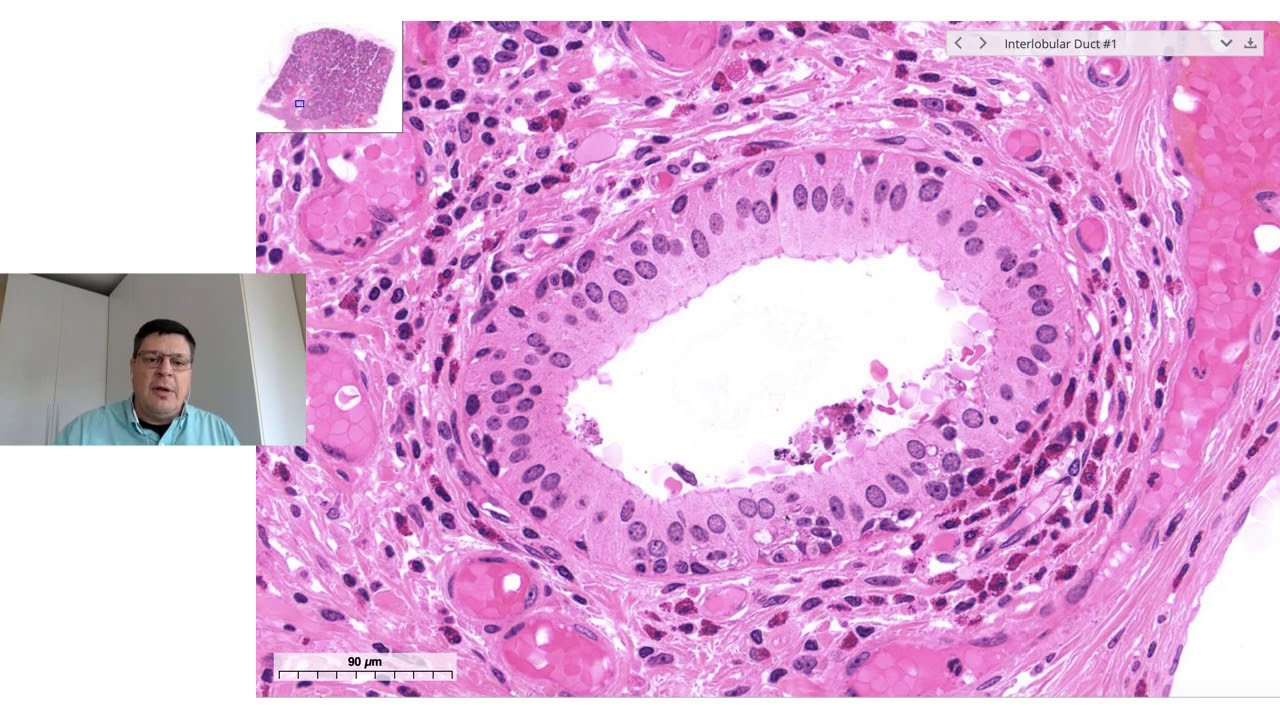

corados eles têm a presença de das chamadas células centroacinares que são células meio que é perdidas dentro do no centro desse assassino que dá início ao Duque bom então o que que acontece esse assino Produza a sua secreção e esse essa secreção ela é conduzida para fora da glândula através de ductos intercalares que são compostos por epitélio cúbico simples esse como eu já comentei esses ductos intercalares se iniciam a partir dessas células centro lobular centroacinares desculpa que são células é colocalizados no centro dos átomos nós temos nessa lâmina mais alguns exemplos de ductos intercalares aqui

um corte longitudinal de um ducto intercalar é esses ductos intercalares se unem e formam os e saem do lóbulo formando os ductos Inter extra lobulares ou interlobulares que estão fora dos lóbulos e daqui isso vai liberar a secreção do suco pancreático no colédoco que por sua vez vai liberar no intestino no intestino ele vai liberar no duodeno tá então a além dessa parte do pâncreas exócrino nós temos o pâncreas endócrino que é formado pelas ilhotas pancreáticas que é glândula endócrina cordonal então como eu vou diminuir um pouquinho aumento e aí a gente consegue ver em